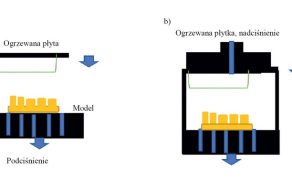

Po 4 miesiącach osseointegracji przeprowadzono drugą fazę chirurgiczną i rozpoczęto zabiegi rehabilitacji protetycznej. Zgodnie [...]